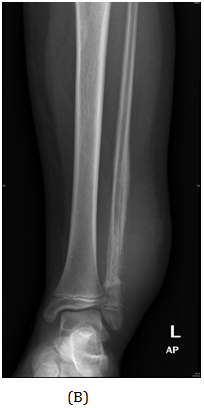

A girl, 11yearsold Saudi presented to us with progressive swelling of the left lower limb, localized above the left ankle with complaints of pain and limping gait. She had visited many clinics for her pain and swelling with no relief to her symptoms. The patient was examined clinically and there was a swelling in the lateral aspect of the distal leg tender firm too hard with intact skin over it, 4x3 cm, no other systemic clinical finding of note. X-ray of the left leg (Figure 1) showed aggressive lytic lesion of the distal fibula. Thence patient was investigated with basic lab works plus systemic and local staging for further diagnosis. She was admitted under us in pediatric surgical ward for open biopsy of the distal fibular lesion and CT of the lower limb (Figure 2) showed destructive bone lesion involving the distal end of the fibula associated with extensive destruction and aggressive periosteal reaction associated with large soft tissue mass 4.5 x 5 cm in maximum axial dimension. Also, MRI of the lower limb (Figure 3) showed there is a large destructive bone lesion involving the distal diaphysis of the left fibula. This lesion does not cross the growth plate. It is associated with aggressive periosteal reaction along with a large soft tissue mass that appears of high signal intensity in T2 and intermediate to low signal intensity in T1 sequences. This was followed by technetium-99m MDP scintigraphy (Figure 4), it showed an increased tracer uptake in the distal left fibula, extending to the left ankle and the left foot. Excisional biopsy was taken from the proximal and distal margin of the lesion in the left fibula which confirmed Ewing's Sarcoma. According to the histopathology department, they reported that there is no evidence of residual tumor i.e free resection margins. (Figure 5) The patient was referred from us to pediatric oncology clinic for further evaluation. She was electively admitted to the hospital for staging and central line insertion to start chemotherapy. She treated as per Ewing sarcoma protocol in our hospital. Patient was put on neoadjuvant chemotherapy which included vincristine, cyclophosphamide, doxorubicin and etoposide, and if osfamide 3 times weekly. After 6 months of chemotherapy, we recommend to her family to do a surgery. We did a wide surgical resection of the tumor in the left leg. Subcutaneous tissue was dissected and isolation of superficial peroneal nerve was done. Dissection of lateral compartment of the left leg up to 16cm proximal to the lateral malleolus and distally, until the distal physis (Figure 6). The tendons of the peroneus longus, peroneus brevis, and flexor halluces longus were sacrificed and the ruminants were used to reconstruct for the lateral aspect of the left ankle using suture anchors (Figure 7). K-wires were used to do temporary arthrodesis (Figure 8). The surgical wound was closed in layers. VAC dressing was also applied as standard care management in Oncology cases at KFMC and backs lab was applied (Figure 9). The last MRI done for the patient showed there is altered signal intensity of the soft tissue with post-contrast enhancement. However, the dimensions of this area of altered signal intensity are decreased as compared to previous MRI. There is no evidence of soft tissue mass lesion (Figure 10). According to the last patient's follow up after six months post-operation it shows no Valgus deviation, normal ankle motion, mobilizing full weight bearing with splint assistant during physical examination (Figure 11). Also, X-rays and MRI finding shows no residual mass lesion or local recurrence.

Figure 1 AP view of plain X-ray of the left leg showed ill-defined lesion involved distal end of the fibula (diaphysis) with cortical destruction and soft tissues swelling.